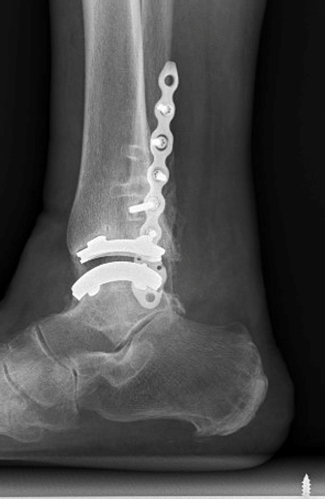

TOTAL ANKLE REPLACEMENT :: ORIF CALCANEUS :: ORIF ANKLE FRACTURE DISLOCATION :: COMPLEX BUNION AND LESSER TOE CORRECTION :: TALUS FRACTURE -1 :: TALUS FRACTURE -2 :: LISFRANC REPAIR :: COMPLEX TRIPLE ARTHRODESIS 1 :: COMPLEX TRIPLE ARTHRODESIS 2 :: MINIMALLY INVASIVE BUNION REPAIR 1 :: MINIMALLY INVASIVE BUNION REPAIR 2 :: ARTHROSCOPIC CARTILAGE REPAIR :: TENEX SPUR DEBRIDEMENT :: Haglunds Debridement and Achilles Repair